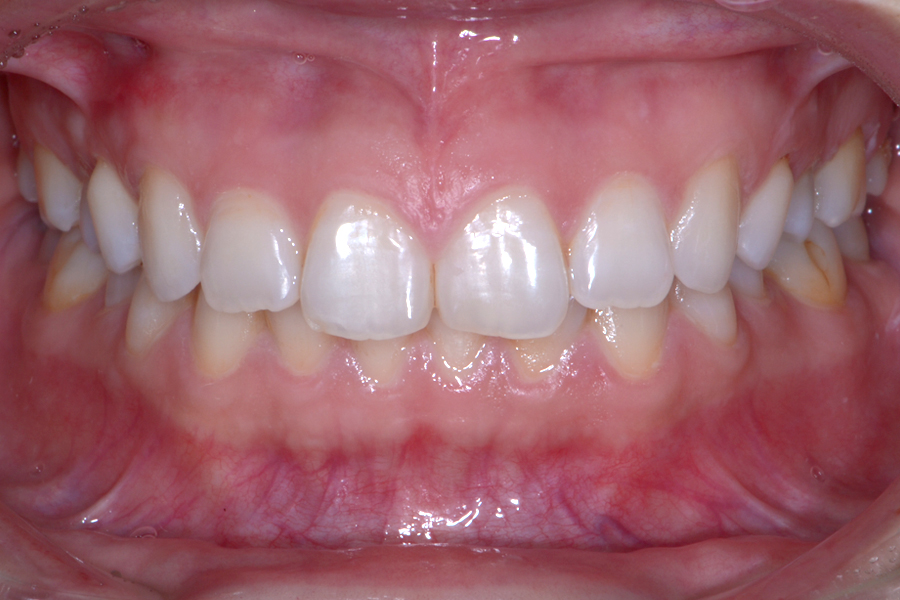

• 治療前

治療後

主訴 前歯のガタツキを治して前歯でものを咬み切れるようになりたい

治療内容 ハーフリンガル矯正(上顎裏側・下顎表側矯正)

リスク 後戻り